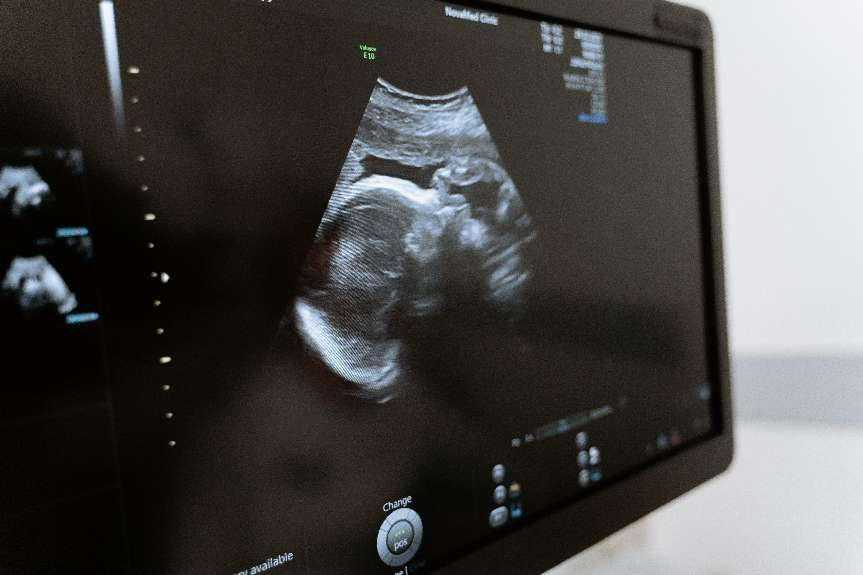

乳腺疾病检查常用的方法有哪些?乳腺疾病常用的影像学检查红外线、B超、钼靶摄片、CT、MRT、PET/放射性核素等。其中B超属无创、方便、无盲区,适合所有人群,能较真实反应肿物的大小,是乳腺体检时最常用的方法。而困扰各位准妈妈最多的是乳腺B超报告中BI-RADS分级。以下为大家揭开乳腺BI-RADS分级的神秘面纱。